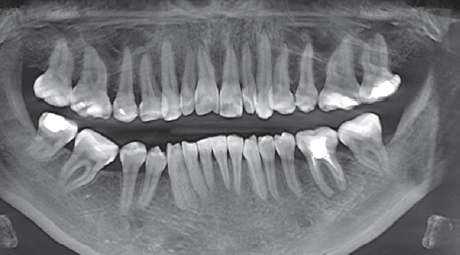

Computed tomography (CT) of the jaws, lateral cephalometric radiographs, TMJ CT, and functional diagnostic tests were performed (Figs. 4–6).

Fig. 5. Section of computed tomography of the jaws before treatment.

Рис. 5. Срез компьютерной томограммы челюстей до лечения.